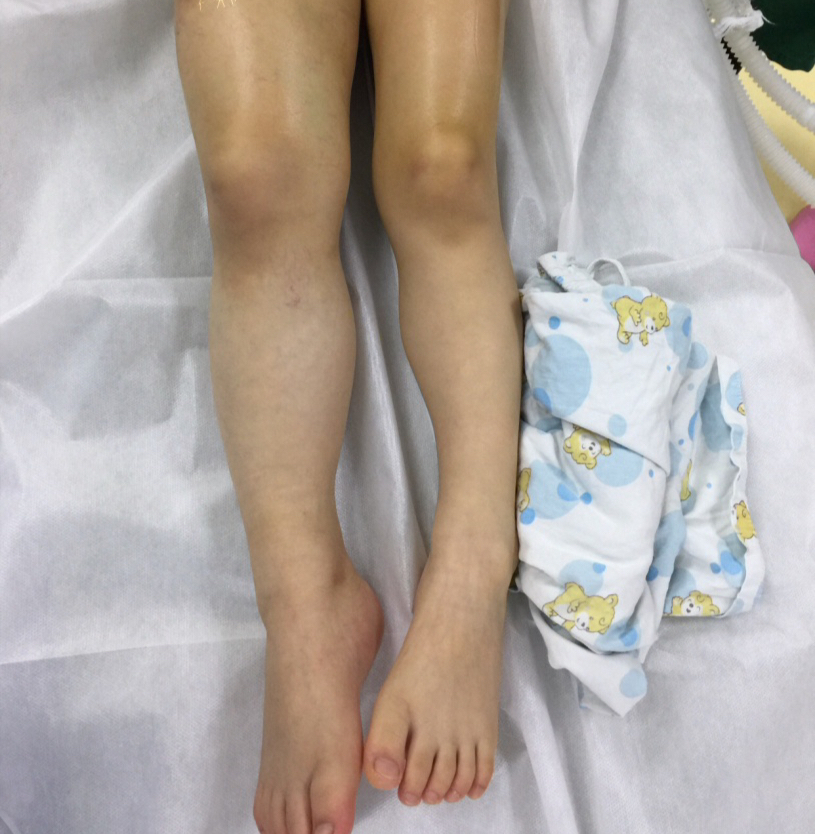

右下肢静脉畸形-微创药物硬化治疗 静脉畸形又称海绵状血管瘤,先天性

图片尺寸1280x1706